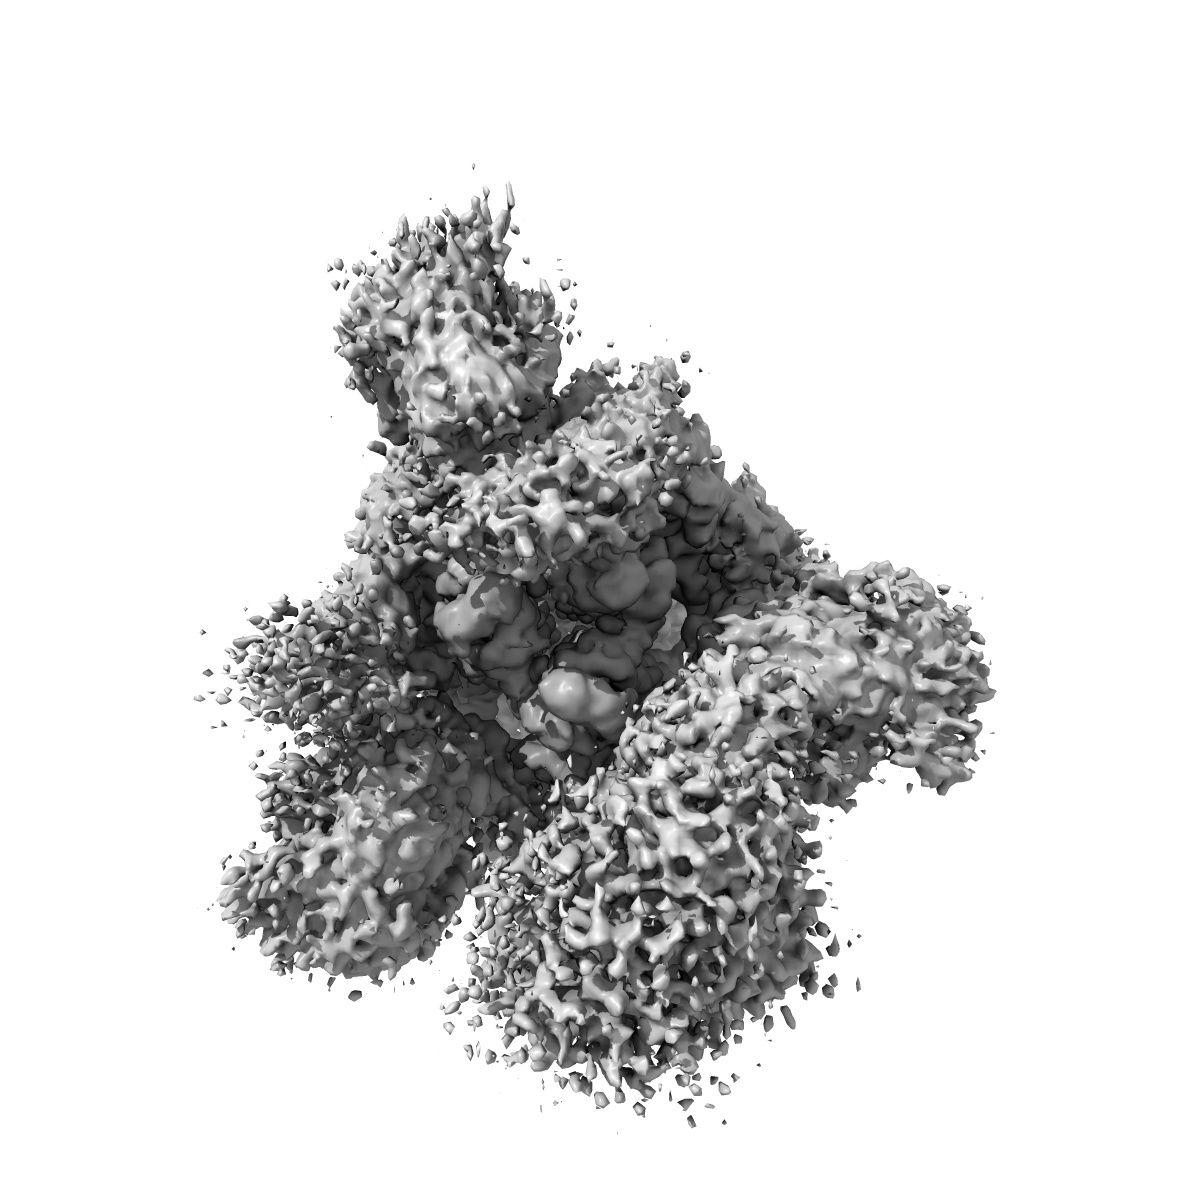

Cryo-EM structure of the SARS-CoV-2 D614G,L452R mutant spike protein ectodomain bound to human ACE2 ectodomain (global refinement)

Sample: SARS-CoV-2 D614G,L452R mutant spike protein ectodomain bound to human ACE2 ectodomain

Structural analysis of receptor binding domain mutations in SARS-CoV-2 variants of concern that modulate ACE2 and antibody binding.

Mannar D, Saville JW , Zhu X , Srivastava SS , Berezuk AM, Zhou S, Tuttle KS, Kim A, Li W, Dimitrov DS, Subramaniam S

(2021) Cell Rep , 37 , 110156 - 110156